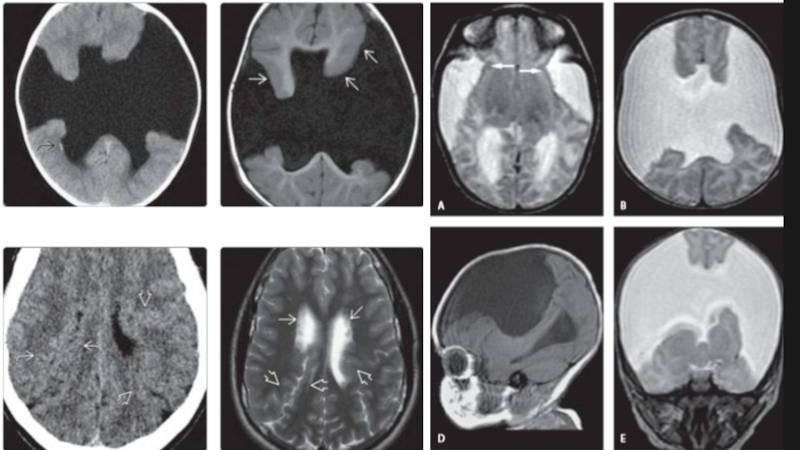

Слайд 23Алобарная голопрозэнцефалия

Алобарная голопрозэнцефалия

Слайд 24Голопрозэнцефалия

Неполное разделение полушарий головного мозга

Визуализация: -единственный желудочек

-отсутствие или частичное базальное и полушарное расщепление в сочетании с отсутствием/неполным развитием межполушарной борозды/серпа мозга

-непарная передняя мозговая артерия

Выраженность и тяжесть аномалии определяется

степенью расщепления переднего мозга

алобарная ГПЭ

семилобарная ГПЭ

лобарная ГПЭ

ГолопрозэнцефалияНеполное разделение полушарий головного мозгаВизуализация: -единственный желудочек

Слайд 32Полимикрогирия

Полимикрогирия

Слайд 33

Проявления кортикальной дисплазии на МРТ различны: неровная, неправильно сформированная поверхность

или наоборот, совершенно гладкая из-за спаянности наружного листка коры (молекулярного

слоя) на микрощелях.

характерна изоинтенсивность

Т2:Полимикрогирия

(два паттерна визуализации)

<12 месяцев: слабо волнистый слой коры нормальной толщины(3-4 мм)

>18 мес. - толстая бугристая кора(6-8 мм), +-расширение периваскулярных пространств+-складчатость коры.

Проявления кортикальной дисплазии на МРТ различны: неровная, неправильно сформированная поверхность или наоборот, совершенно гладкая из-за спаянности наружного

Слайд 34Шизэнцефалия

При I типе края расщелины широко

отстоят

друг от друга, пространство

между ними заполнено ликвором.

При шизэнцефалии II типа края

расщелины сомкнуты, плотно прилежат

друг к другу, разделяясь глубокой узкой

бороздой, выстланной эпендимой и

паутинной оболочкой.

Деструкция коры мозга при

шизэнцефалии сопровождается гетеротопией серого вещества по краям расщелины.

Шизэнцефалия При I типе края расщелины широко   отстоят друг от друга, пространство   между